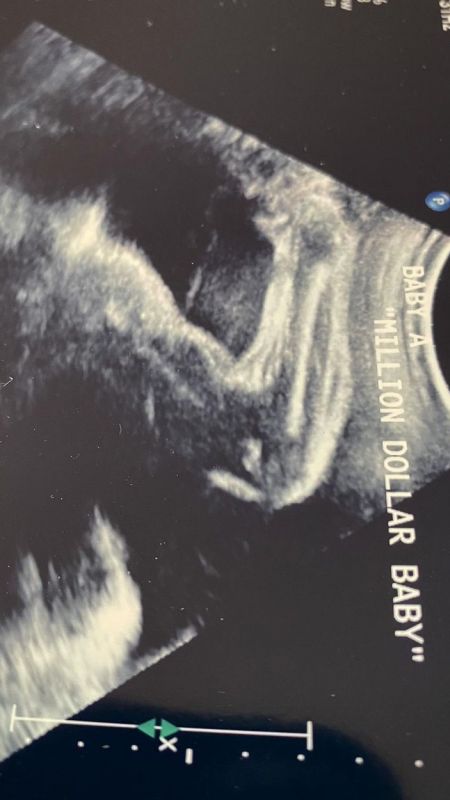

Son gelişme elbette Hilary Swank'ın önümüzdeki ay ikiz bebek beklediği haberi. 48 yaşındaki aktris, ilk kez anne olmaya hazırlanıyor ve hayatına iki küçük neşe demeti katacağı için çok mutlu.

Hilary Swank, bu güzel haberi sosyal medya üzerinden hayranları ile paylaştı. Fotoğraftaki en önemli ayrıntı Hilary Swank’ın ikizlerinin olacağı bilgisi idi. Bu haber güzel oyuncunun hayranlarını sevinçten ağlattı. Swank’ın bu paylaşımı çok sayıda yorum ve beğeni alırken bazı yorumlarda ünlü oyuncuya mutluluklar dilendiği görüldü. Şimdi Hilary Swank’ın tüm hayranları doğumdan sonra ikizlerin fotoğrafını bekliyor.